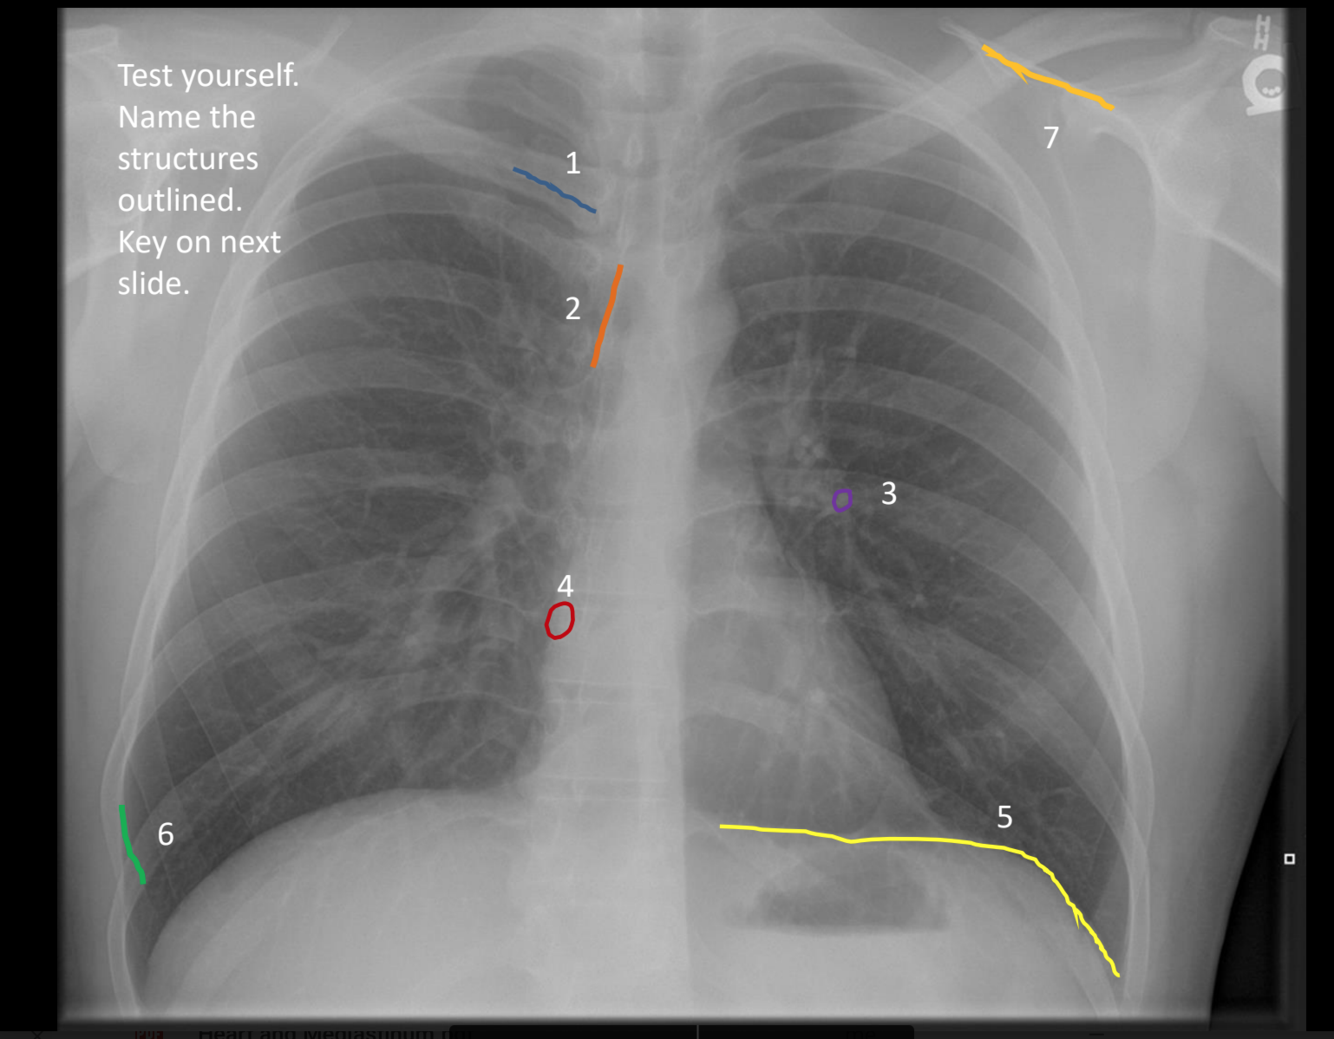

what is 7?

spine of left scapula

what is 6?

superior margin of anterior right rib 9

what is 5?

left hemidiaphragm

what is 4?

posterior clear space

what is 2?

anterior clear space